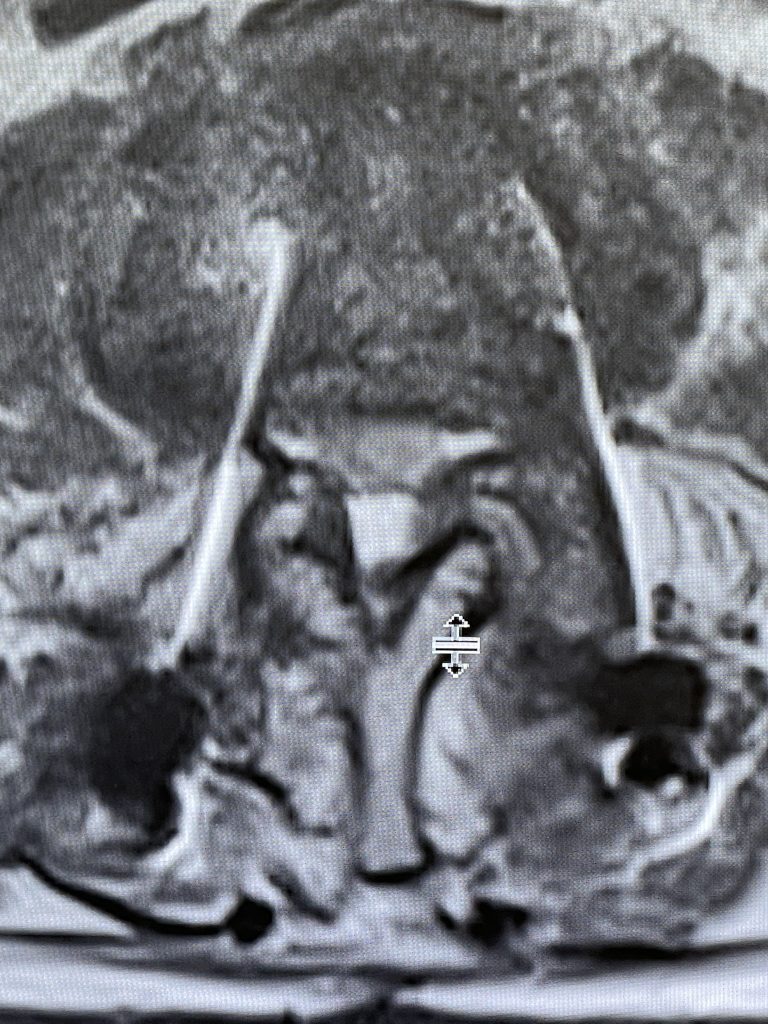

During the decompression we removed the inferior facets of L2 after the L3 screws were removed. This is a key maneuver in a revision decompression as it allows access to a dissection plane that allows the foramina and both L3 nerve roots to safely be decompressed. The L2 lamina is removed as well as a dissection plane at the inferior aspect of the bone is developed with an up biting curette. Because of her solid fusion it was only necessary to add new screws at L2 and L3 giving her a shorter construct and less potential stress at the next segment. Post operatively the patient did very well with resolution of leg pain and improved strength in her proximal leg strength. (Figure 3)